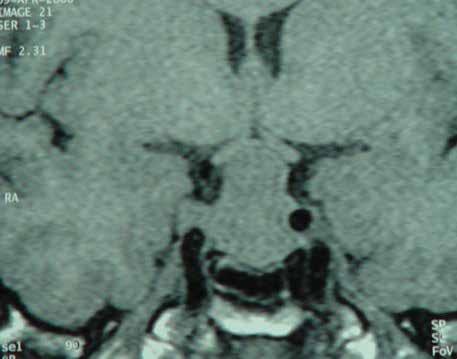

Figure 4. Multimodal imaging of a female diabetic patient affected by PDR that has already undergone complete laser photocoagulation treatment. 4A) UWF pseudocolor retinography showing complete laser photocoagulation treatment until vascular arcades; 4B-C) 12x12 and 4E-F) en-face WF-SS-OCTA of diabetic patient (4B, 4E) presenting FAZ enlargement, diffuse capillary drop-out and inferior mid-peripheral retinal nonperfusion areas, as compared to healthy patient (4C, 4F; 4D) Late phase UWF FA displaying diffuse BRB breakdwon, with perivascular leakage and non-perfusion areas.